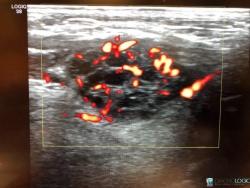

18 yr old for USG neck- Altered thyroid funtion See more

Lingual thyroid( ectopic thyroid) with secondary colloid goiter changes See more